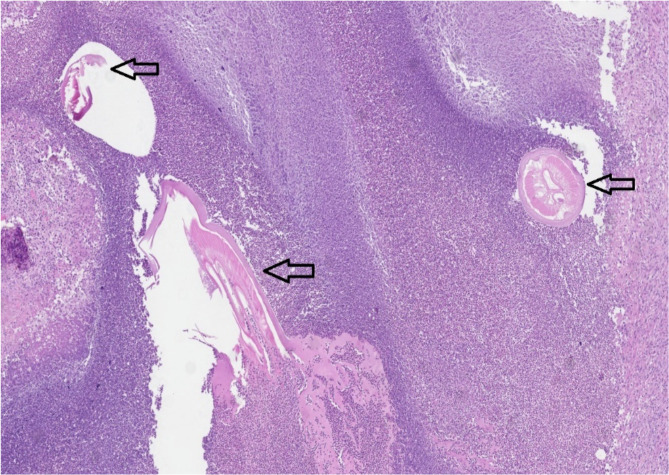

Human dirofilariasis is a rare anthropo-zoonotic disease, mainly detected in Southern and Eastern Europe, Asia Minor, Central Asia, and Sri Lanka. An increasing number of autochthonous Dirofilaria spp. infections has been recently reported in the areas previously considered free of the disease, including northern Europe and the Baltic States. A rare autochthonous case of scrotal dirofilariasis detected in Lithuania was described. Here, a 42-year-old male presented with a 1 cm nodule, limited in the scrotum. A nodule excision was performed. On histological examination, a degenerating roundworm with the features of Dirofilaria spp. (multilayered cuticle, well-developed musculature, focally preserved longitudinal ridges) was detected in the abscess cavity. No additional treatment was needed. Twenty-four publications reporting 28 male genitalia dirofilariasis cases in European countries have been identified.